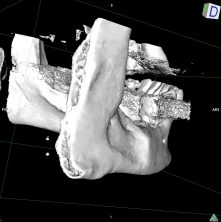

L’intervention chirurgicale consiste en une reconstruction osseuse du maxillaire ou de la mandibule avant la mise en place des implants dentaires par votre chirurgien.